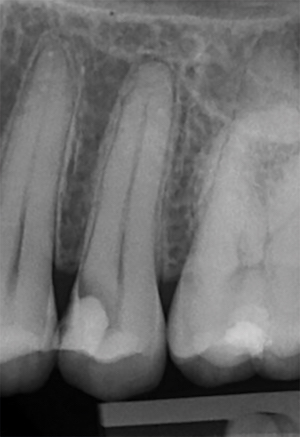

Face à une carie à un stade avancé, sur quels critères cliniques s’appuyer pour conserver la vitalité pulpaire ?

- Biopulpectomie ou coiffage pulpaire ?